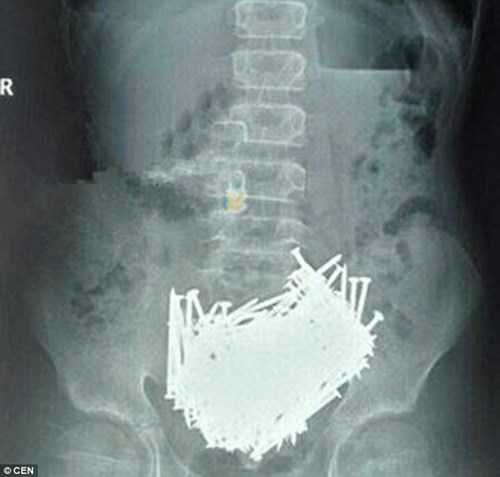

Một cậu bé 15 tuổi ở Giang Tây, Trung Quốc nhập viện trong tình trạng đau bụng dữ dội. Tại bệnh viện, cậu bé này được cho đi chụp CT. Kết quả chụp khiến các bác sĩ vô cùng hoảng hốt. Họ phát hiện cậu bé có hàng trăm dị vật lạ trong dạ dày bằng kim loại giống như những chiếc đinh.

Hình chụp CT có thể thấy rõ 200 chiếc đinh nằm trong bụng cậu bé 15 tuổi.

Ngay lập tức các bác sĩ đưa em tới phòng phẫu thuật và lấy ra rất nhiều dị vật khủng khiếp gồm hơn 200 chiếc đinh, tăm xỉa răng, đá và tiền xu. Bác sĩ cho biết: Cậu bé mắc này mắc chứng Pica. Trong suốt nhiều năm làm nghề y, chưa bao giờ họ thấy ca bệnh nào tương tự như vậy.

200 chiếc đinh được lấy ra khỏi bụng cậu bé 15 tuổi ở Trung Quốc.

Đây là một hội chứng rối loạn sức khỏe tâm thần. Những người mắc chứng bệnh này luôn thấy thèm không thể cưỡng lại được những thứ không phải là thức ăn như bụi bẩn, giấy, than đá, phấn, đất, hồ dán, kim loại...".